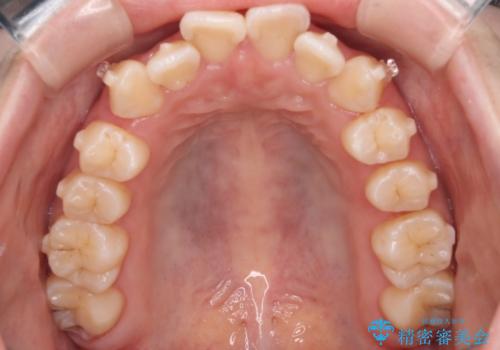

【インビザライン】マウスピースで開咬改善

- 開咬を主訴に来院されました。

IPR(歯と歯の間を削る処置)と顎間ゴムを行いながら、インビザラインで開咬を治療する計画を立てました。

治療をしながら、MFT(口腔筋機能療法)も行っていくことにしました。

歯の移動量が多いケースでしたが、患者様にマウスピースの使用とゴム掛けを頑張っていただいたので

リファイメント1回のみで治療を終わることができました。